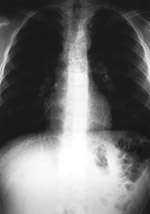

Bingo chip in hypopharynx |

2 year-old girl with severe respiratory symptoms. She had a left sided pneumonia and empyema requiring a tracheostomy. For several days the ring-like metallic density noted on her portable chest radiograph was assumed to be associated with her tracheostomy. The above lateral and frontal chest radiographs reveal the metallic density is not associated with the tracheostomy. A bingo chip was removed at endoscopy. From Hunter, 1994 |